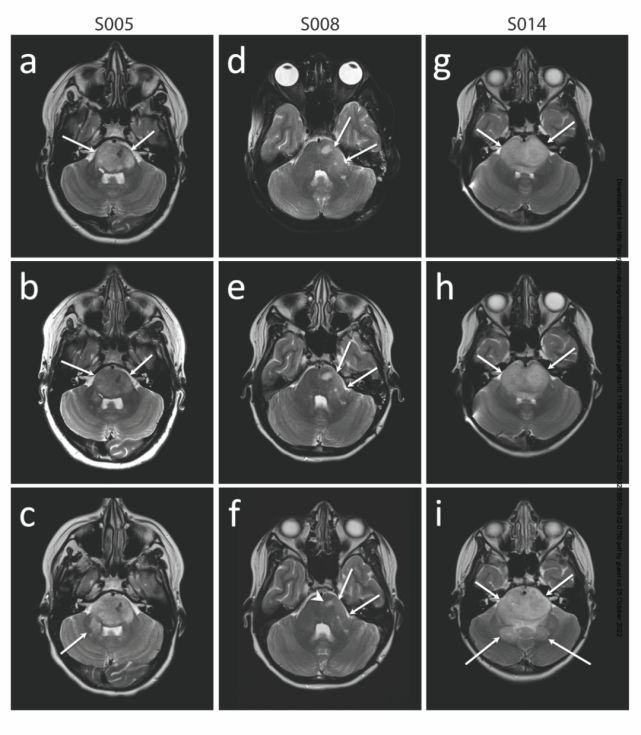

患者在接受完两个治疗疗程(8周)会做神经影像检查。S005与S014是在肿瘤出现进展后入组,两位患者经过6个月的治疗,在影像上出现了肿瘤体积增加,对应了细胞浸润到右侧脑桥臂(right brachium pontis)。而S008是在肿瘤进展前入组,接受CAR T治疗后在影像上出现了肿瘤体积轻度缩小。到第八次CAR T输入时,患者已有临床症状上的改善,改善一直持续到加入试验12个月后,此时患者决定终止试验,回到自己本地的机构治疗。

3位患者接受治疗后不同时间的影像跟踪